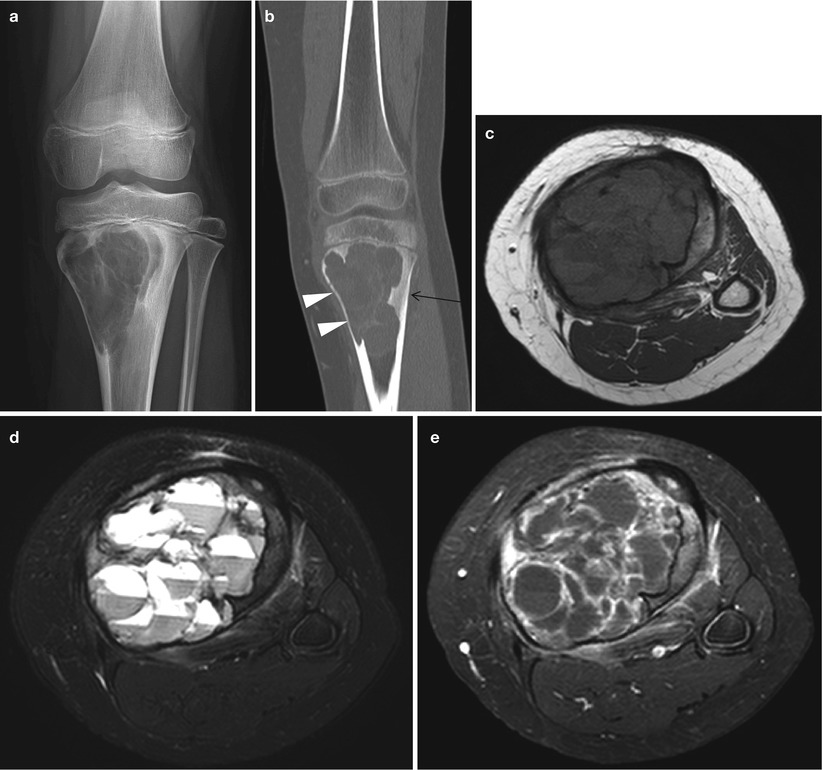

WebAbstract. Although primary bone tumors are relatively uncommon, appropriate imaging evaluation is essential when they are suspected or incidentally detected. In almost all cases, radiographs are the most appropriate initial imaging study for screening and characterization of primary bone tumors.